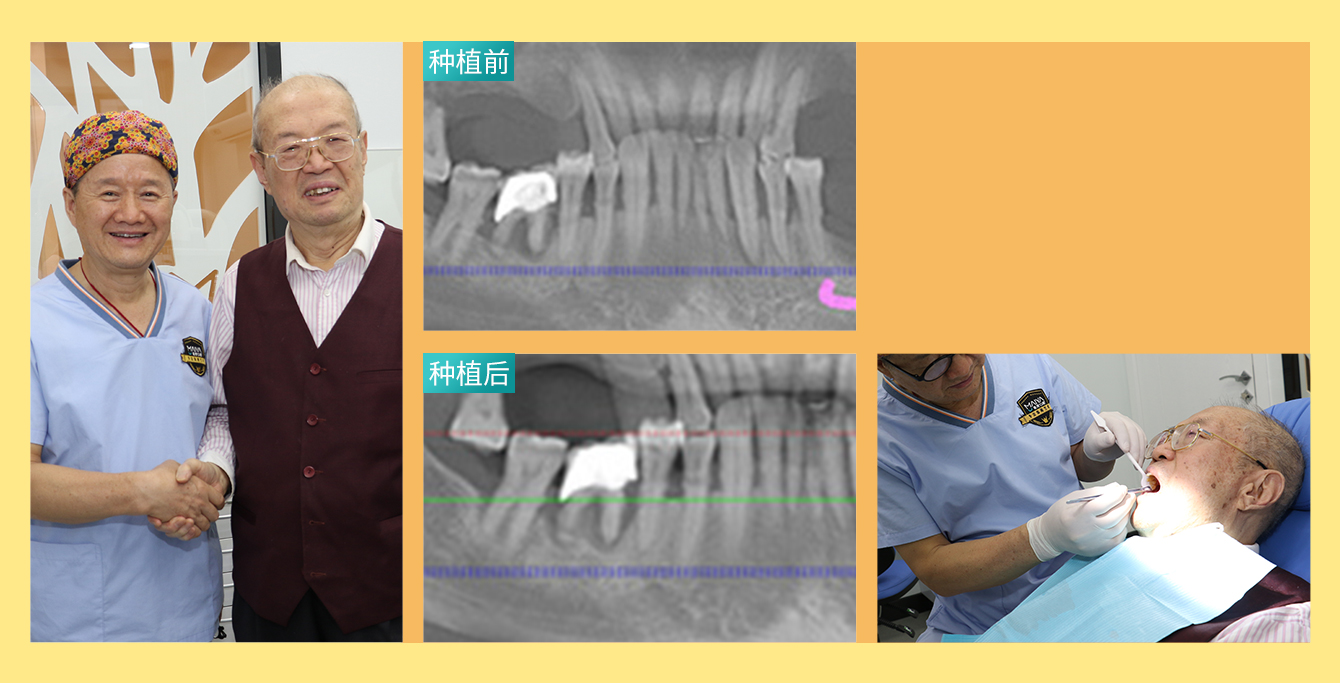

• 种牙人:TVB演员古明华

年龄:61岁

主诉:上半口牙缺失

种牙方式:ALL ON- 6种植技术

代表作:《法正先锋》 、《陀枪师姐》